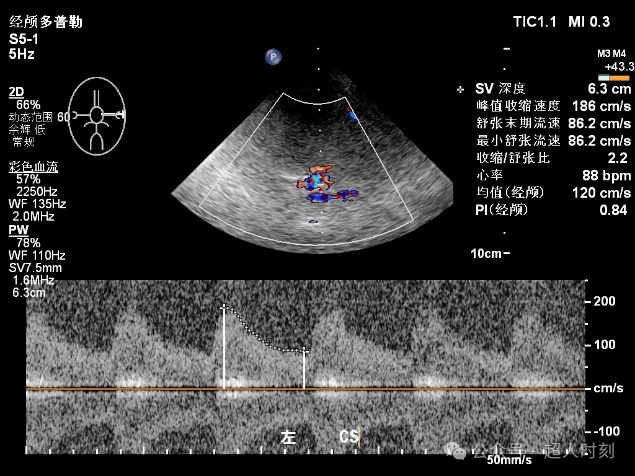

TCCD(图3)不仅能够得到TCD那样的频谱图,还能直观看到血管的走行和血流的状态,是可视化医学的一个明显特征。

图5g左颈内动脉虹吸部狭窄血流频谱(VP:186cm/s)